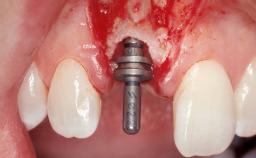

Late Placement of an Implant in a Maxillary Left Central Incisor Site

Type of Implants Two-Piece

Bone Augmentation Horizontal|Staged

Augmentation Materials Xenogenous|Membrane

Placement Protocol Early or late implant placement